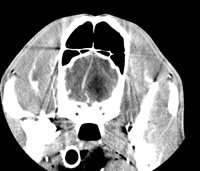

Encéphale

- Exploration des crises d'épilepsie et des Syndromes convulsifs

- Exploration des modifications comportementales subites inexpliquées

- Exploration des altérations de l'état de vigilance

- Exploration des accidents vasculaires cérébraux

- Traumatismes crâniens

- Exploration des syndromes de Cushing d'origine hypophysaire

- Amaurose (perte de la vue)

- Suspicion de maladies congénitales : Hydrocéphalie, dysplasie occipitale...

- Suspicion de tumeur cérébrale